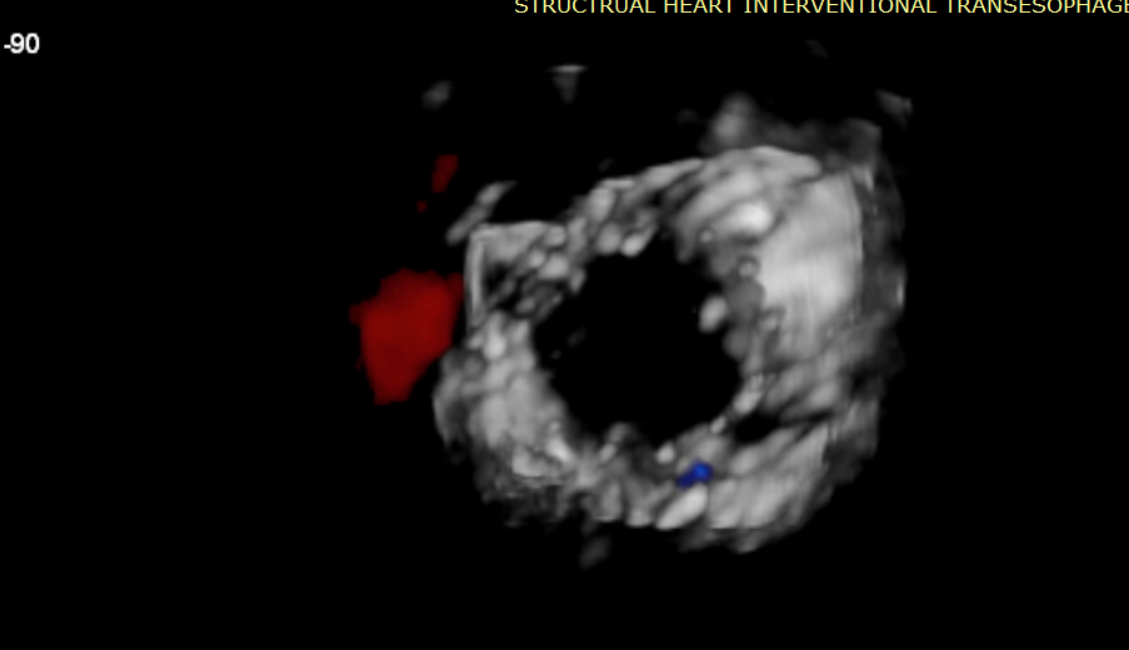

術(shù)前超聲提示大量三尖瓣反流

術(shù)后超聲提示無(wú)瓣周漏